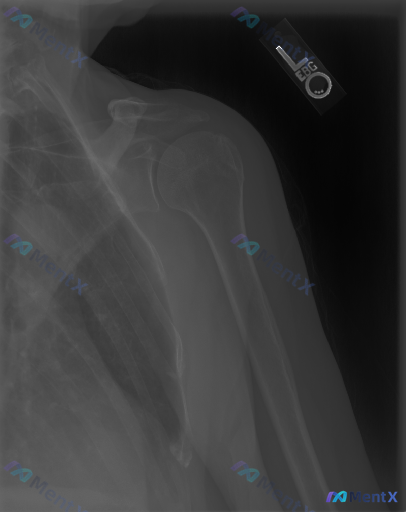

整理了一份左侧肩部正位X光片的临床分析资料,有点意思: 影像上明确说了: - 肱骨头、肩胛盂、锁骨这些骨性结构都完整,没骨折、没脱位、没骨质破坏 - 关节间隙好,没有明显骨赘、囊性变 - 肩袖附着区没看到钙化 - 软组织也没明显肿胀、积气 - 一句话:未见明确骨性异常 但问题来了:如果这个患者是因为...

整理到一份右肩关节正位X光片的资料,先抛出来和大家讨论下读片和后续思路。 先看影像的客观表现: - 肱骨近端、锁骨远端、肩胛骨各部位骨皮质连续,未见明确骨折线、脱位或半脱位 - 盂肱关节、肩锁关节间隙基本正常,对合可 - 肩峰下间隙等未见明显狭窄或异常钙化 - 无明显退行性骨关节炎或骨质密度异常 影...

整理到一份挺有启发的读片对照: 用户原始问题是「这张图像中可以观察到什么异常?存在异常」,先入为主给了「有异常」的暗示。 但实际影像资料是一张标准右肩胛骨Y位X光片——投照质量良好,Y字形结构完整,肱骨头在肩胛盂窝处居中,喙突、肩峰、肩胛体、肱骨近端都没看到明确骨折线、脱位或骨质破坏,关节间隙也正常...